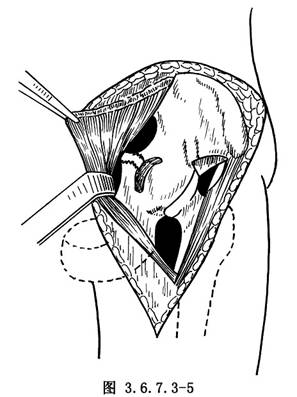

11.2 2.顯露髂前窩和髖臼骨折部

在髂骨嵴上開始做髂骨內板骨膜下剝離,從外側向內側剝離軟組織,分割向下,進入髂前窩,將髂腰肌向內側牽開,將內臟一併牽向骨盆對側,如見髖臼底骨折塊卡住股骨頭,則用剝離子輕輕剝離移動骨折塊,使股骨頭解脫卡壓,還納股骨頭,用手法將臼底骨折塊復位,用骨錘輕輕敲擊復位骨塊,使其緊密嵌合(圖3.6.7.3-5)。